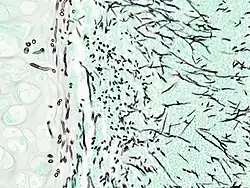

| Pulmonary invasive aspergillosis in a person with interstitial pneumonia (autopsy material), using Grocott's methenamine silver stain | |

On microscopy, Aspergillus species are reliably demonstrated by silver stains, e.g., Gridley stain or Gomori methenamine-silver.[27] These give the fungal walls a gray-black colour. The hyphae of Aspergillus species range in diameter from 2.5 to 4.5 μm. They have septate hyphae,[28] but these are not always apparent, and in such cases they may be mistaken for Zygomycota.[27] Aspergillus hyphae tend to have dichotomous branching that is progressive and primarily at acute angles of around 45°.[27]